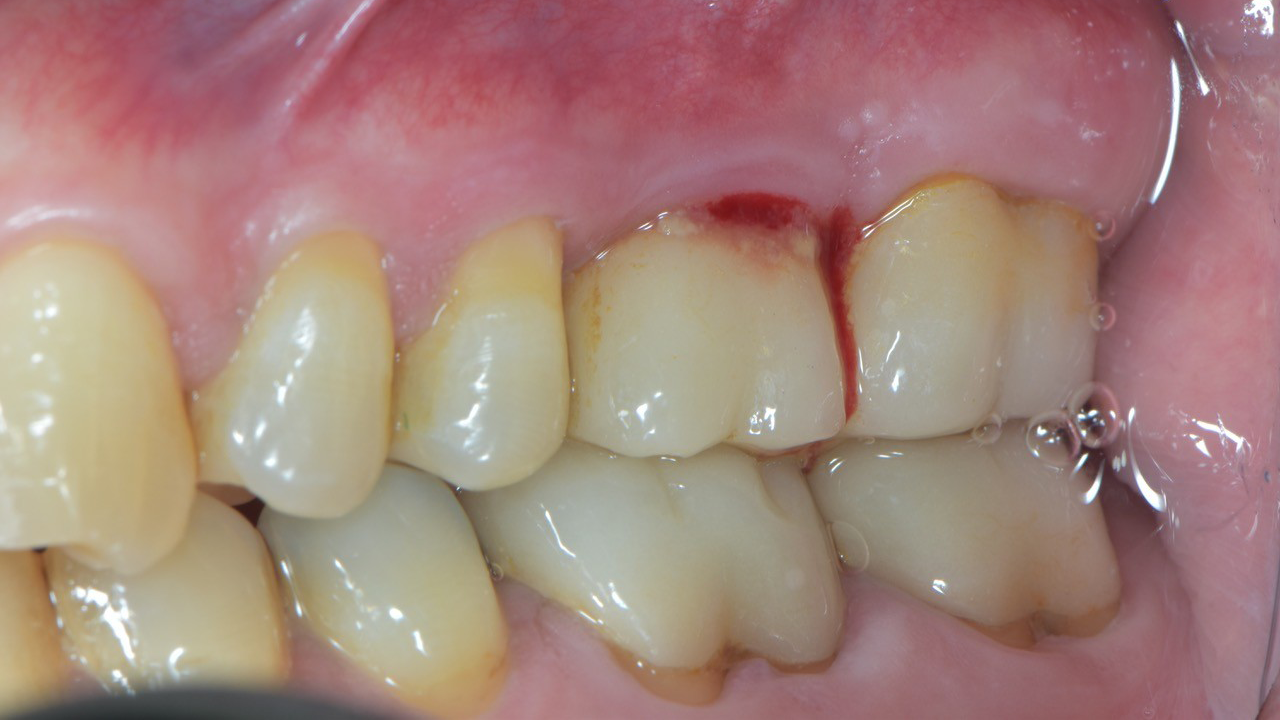

Periimplantitis stellt eine der bedeutendsten biologischen Komplikationen implantatgetragener Versorgungen dar und gefährdet langfristig die Stabilität und Prognose dentaler Implantate. Diese Falldiskussion beleuchtet Pathogenese, Risikofaktoren sowie diagnostische Kriterien und zeigt anhand klinischer Beispiele, wie ein strukturiertes therapeutisches Vorgehen entwickelt werden kann. Dabei werden sowohl nicht-chirurgische als auch chirurgische Behandlungsansätze bewertet und deren Wirksamkeit im individuellen Fall reflektiert. Die Analyse unterstreicht die Bedeutung frühzeitiger Intervention und konsequenter Nachsorge, um den fortschreitenden Knochenabbau zu kontrollieren und eine nachhaltige Implantatgesundheit zu sichern.